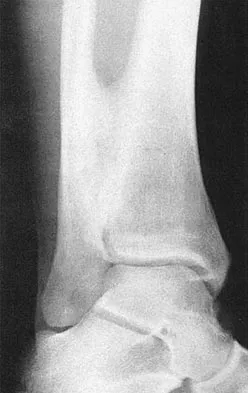

A 28-year-old professional football player reports painless loss of ankle motion after sustaining a "severe" ankle sprain 12 months ago. A mortise radiograph is shown in Figure 1. Surgical treatment should be reserved for which of the following conditions?

Explanation